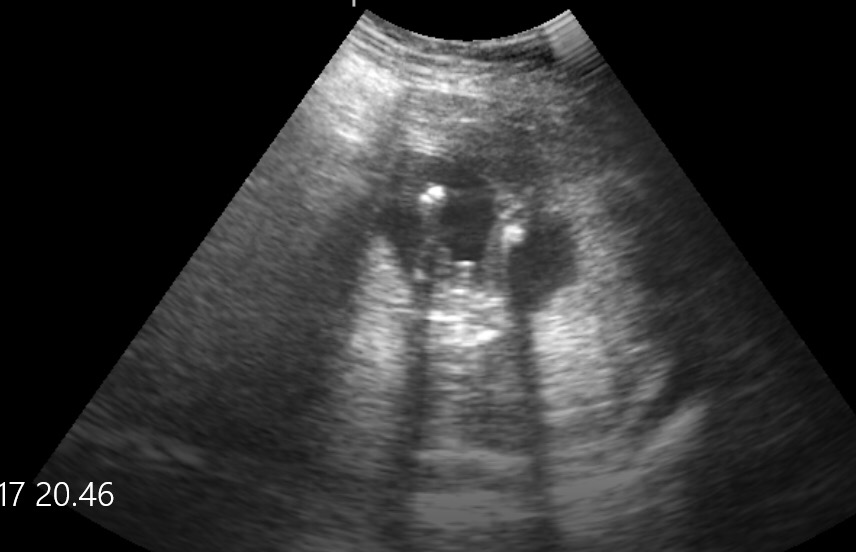

I tought on the first pic, a girl..